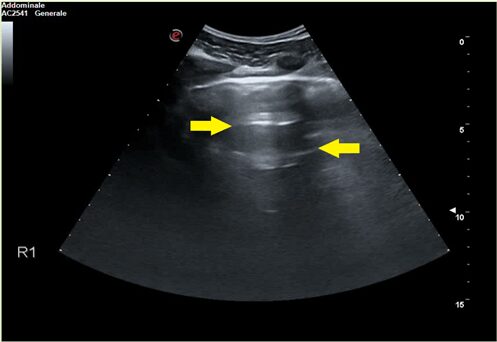

Questa è un’area di tessuto polmonare normale: sono presenti le linee A (frecce gialle) date dalla riflessione degli ultrasuoni sulla pleura.

Figura 3 – SARS-CoV2 ed ecografia: Questa è un’area di tessuto polmonare normale: sono presenti le linee A (frecce gialle) date dalla riflessione degli ultrasuoni sulla pleura. Credit: https://www.efsumb.org/blog/archives/26658 – autori: dott. Soccorsa Sofia e dott. Michele Spampinato

Normalmente il parenchima polmonare non è visibile, perché pieno d’aria, che è anecogena, si vedono solo le cosiddette linee A, artefatti bianchi orizzontali dati dalla riflessione degli ultrasuoni sulla pleura. In caso di polmonite cominciano ad apparire degli artefatti verticali, le cosiddette linee B, che nascondono le linee A e sono dovute al fatto che la porzione di tessuto polmonare esplorata non è areata.